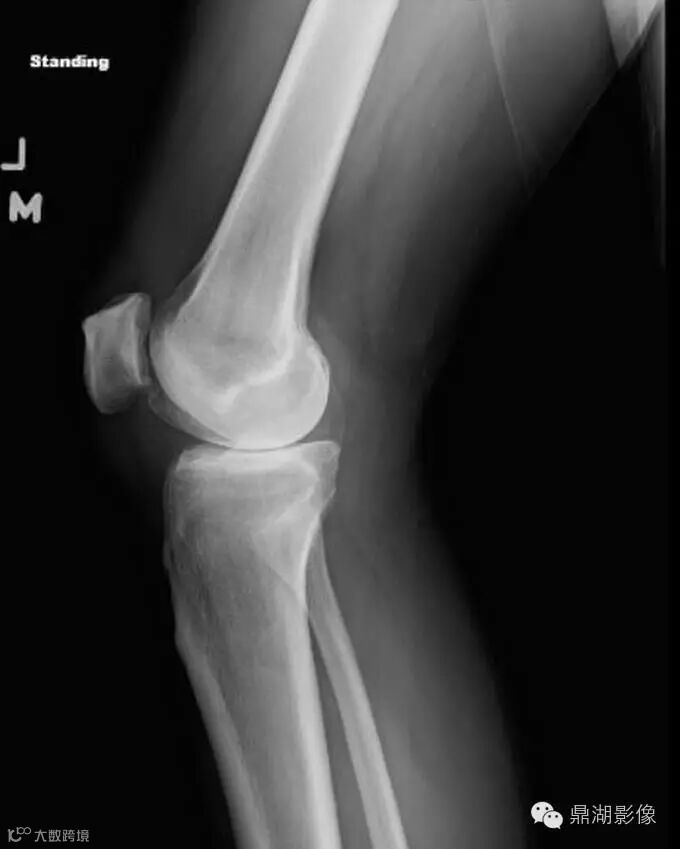

2.1 What is the most accurate explanation for the difference between the current lateral knee radiograph (Figure 1) and lateral radiograph (Figure 2) obtained 2 years earlier?

A. Dystrophic calcification of the soleus muscle due to recurrent trauma

B. A phlebolith within the peroneal vein

C. A calcified body within the inferior recess of a dissecting Baker cyst

D. Soft-tissue sarcoma

Yes, the answer is C

C. The calcified body has migrated distally from its original position posterior to the femoral condyles.

Incorrect. Although dystrophic calcification could have this appearance, it is not the most accurate answer since the calcification has migrated distally from its original position posterior to the femoral condyles.

Incorrect. Although a phlebolith could have this appearance, it is not the most accurate answer since the calcification has migrated distally from its original position posterior to the medial femoral condyle.

Incorrect. This calcification has a benign appearance. Additionally, this would not be the most accurate answer since the calcification has migrated distally from its original position posterior to the medial femoral condyle.

Lateral view of the left knee from two years prior shows the body positioned posterior to the femoral condyles (white arrow).